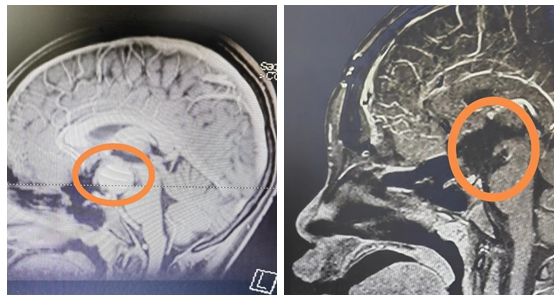

13岁的涵涵身高仅有145cm,体重37kg,比同班的男孩,甚至女孩都要矮小。起初,爸爸妈妈也没有太在意,以为孩子就是“长得晚”。2023年5月份开始,涵涵偶尔会跟爸爸妈妈说自己视物模糊,看不清,这时父母才重视,带涵涵到当地医院就诊。在医生的建议下查了颅脑MRI,问题果然出现在脑袋上,考虑:颅咽管瘤。为寻求手术治疗,涵涵在家长陪同下慕名来到湘雅常德医院神经外科就诊。

入院后,涵涵完善了相关辅助检查,经过袁贤瑞教授团队讨论分析后,为其制定了最适合的手术方式。术前告知家属术中、术后的风险且征得其同意签字确认后,袁贤瑞教授带领神经外科团队在显微镜下行鞍区占位切除术,术中肿瘤全切,手术顺利完成。

颅咽管瘤位于下丘脑和垂体区域,毗邻两大内分泌的中枢,也就是我们说的下丘脑和垂体,上面两侧是脑室,两边是海绵窦,还有颈内动脉,再下面是视神经、视交叉。颅咽管瘤长在脑袋的正中间,周围这么多重要的结构,损伤哪一个都不行,如果损伤了视神经可能引起单侧失明,损伤了视交叉会双侧失明,损伤颈内动脉会带来灾难性的大出血。下面的垂体受到影响,会终生内分泌紊乱,损伤后面的下丘脑不光是带来体温调节障碍,食欲减退,甚至可能导致昏迷。

世界卫生组织称:颅咽管瘤是颅内唯一因为解剖因素而不能治愈的呈恶性结果的良性肿瘤。也就是说,这个良性肿瘤,本该能治好,但因为位置的特殊而极难全切,如果肿瘤不全切,术后极易复发,且对化疗、放疗均不敏感,只能行第二次手术治疗,所以第一次手术能否全切对患者来说至关重要。